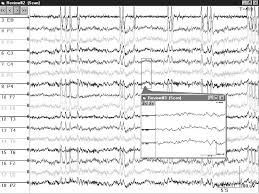

Elettroencefalogramma in veglia, dopo privazione ipnica ed in sonno

L'elettroencefalogramma è la registrazione dell'attività bioelettrica cerebrale ottenuta posizionando dei sensori (elettrodi di superficie) sulla testa.